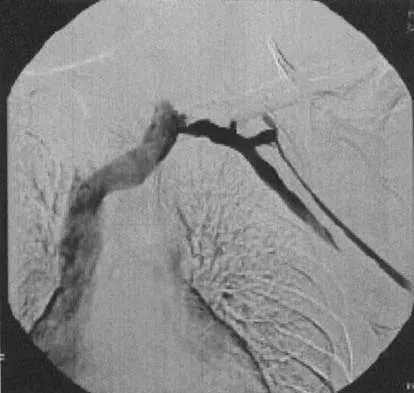

A well-developed college football player reports swelling and a heaviness in the arm after lifting weights. Examination reveals that distal pulses are normal and equal in both arms. A venogram is shown in Figure 13. What is the most likely cause of this condition?